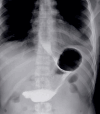

Combining transoral fundoplication and robotic cruroplasty: a novel robotic-assisted endoscopy